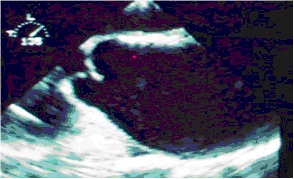

Ecocardiografia transtoracica e transesofageaL’esame ecocardiografico transtoracico è utilissimo negli aneurismi dell’aorta ascendente poiché permette di evidenziare la parete aortica, le caratteristiche dell’aneurisma (sede, forma, diametro, eventuali trombi e calcificazioni endoaneurismatiche, o un’eventuale dissezione), una dilatazione dei seni di Valsalva ed un’eventuale insufficienza valvolare aortica, ma non è altrettanto accurato per gli aneurismi dell’arco e dell’aorta discendente (in tali casi l’ecocardiografia transesofagea è accurata ed ha una specificità pari al 97% e una sensibilità del 99%).